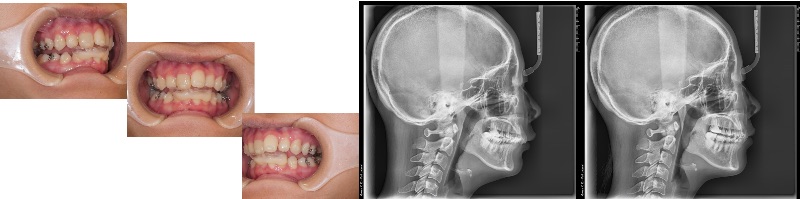

- Qクリンチェックの修正小児矯正

Oさん小学生

治療方針、クリンチェックご指導下さい - A正規会員もしくはQAアクセス会員になると、Aが表示されます。